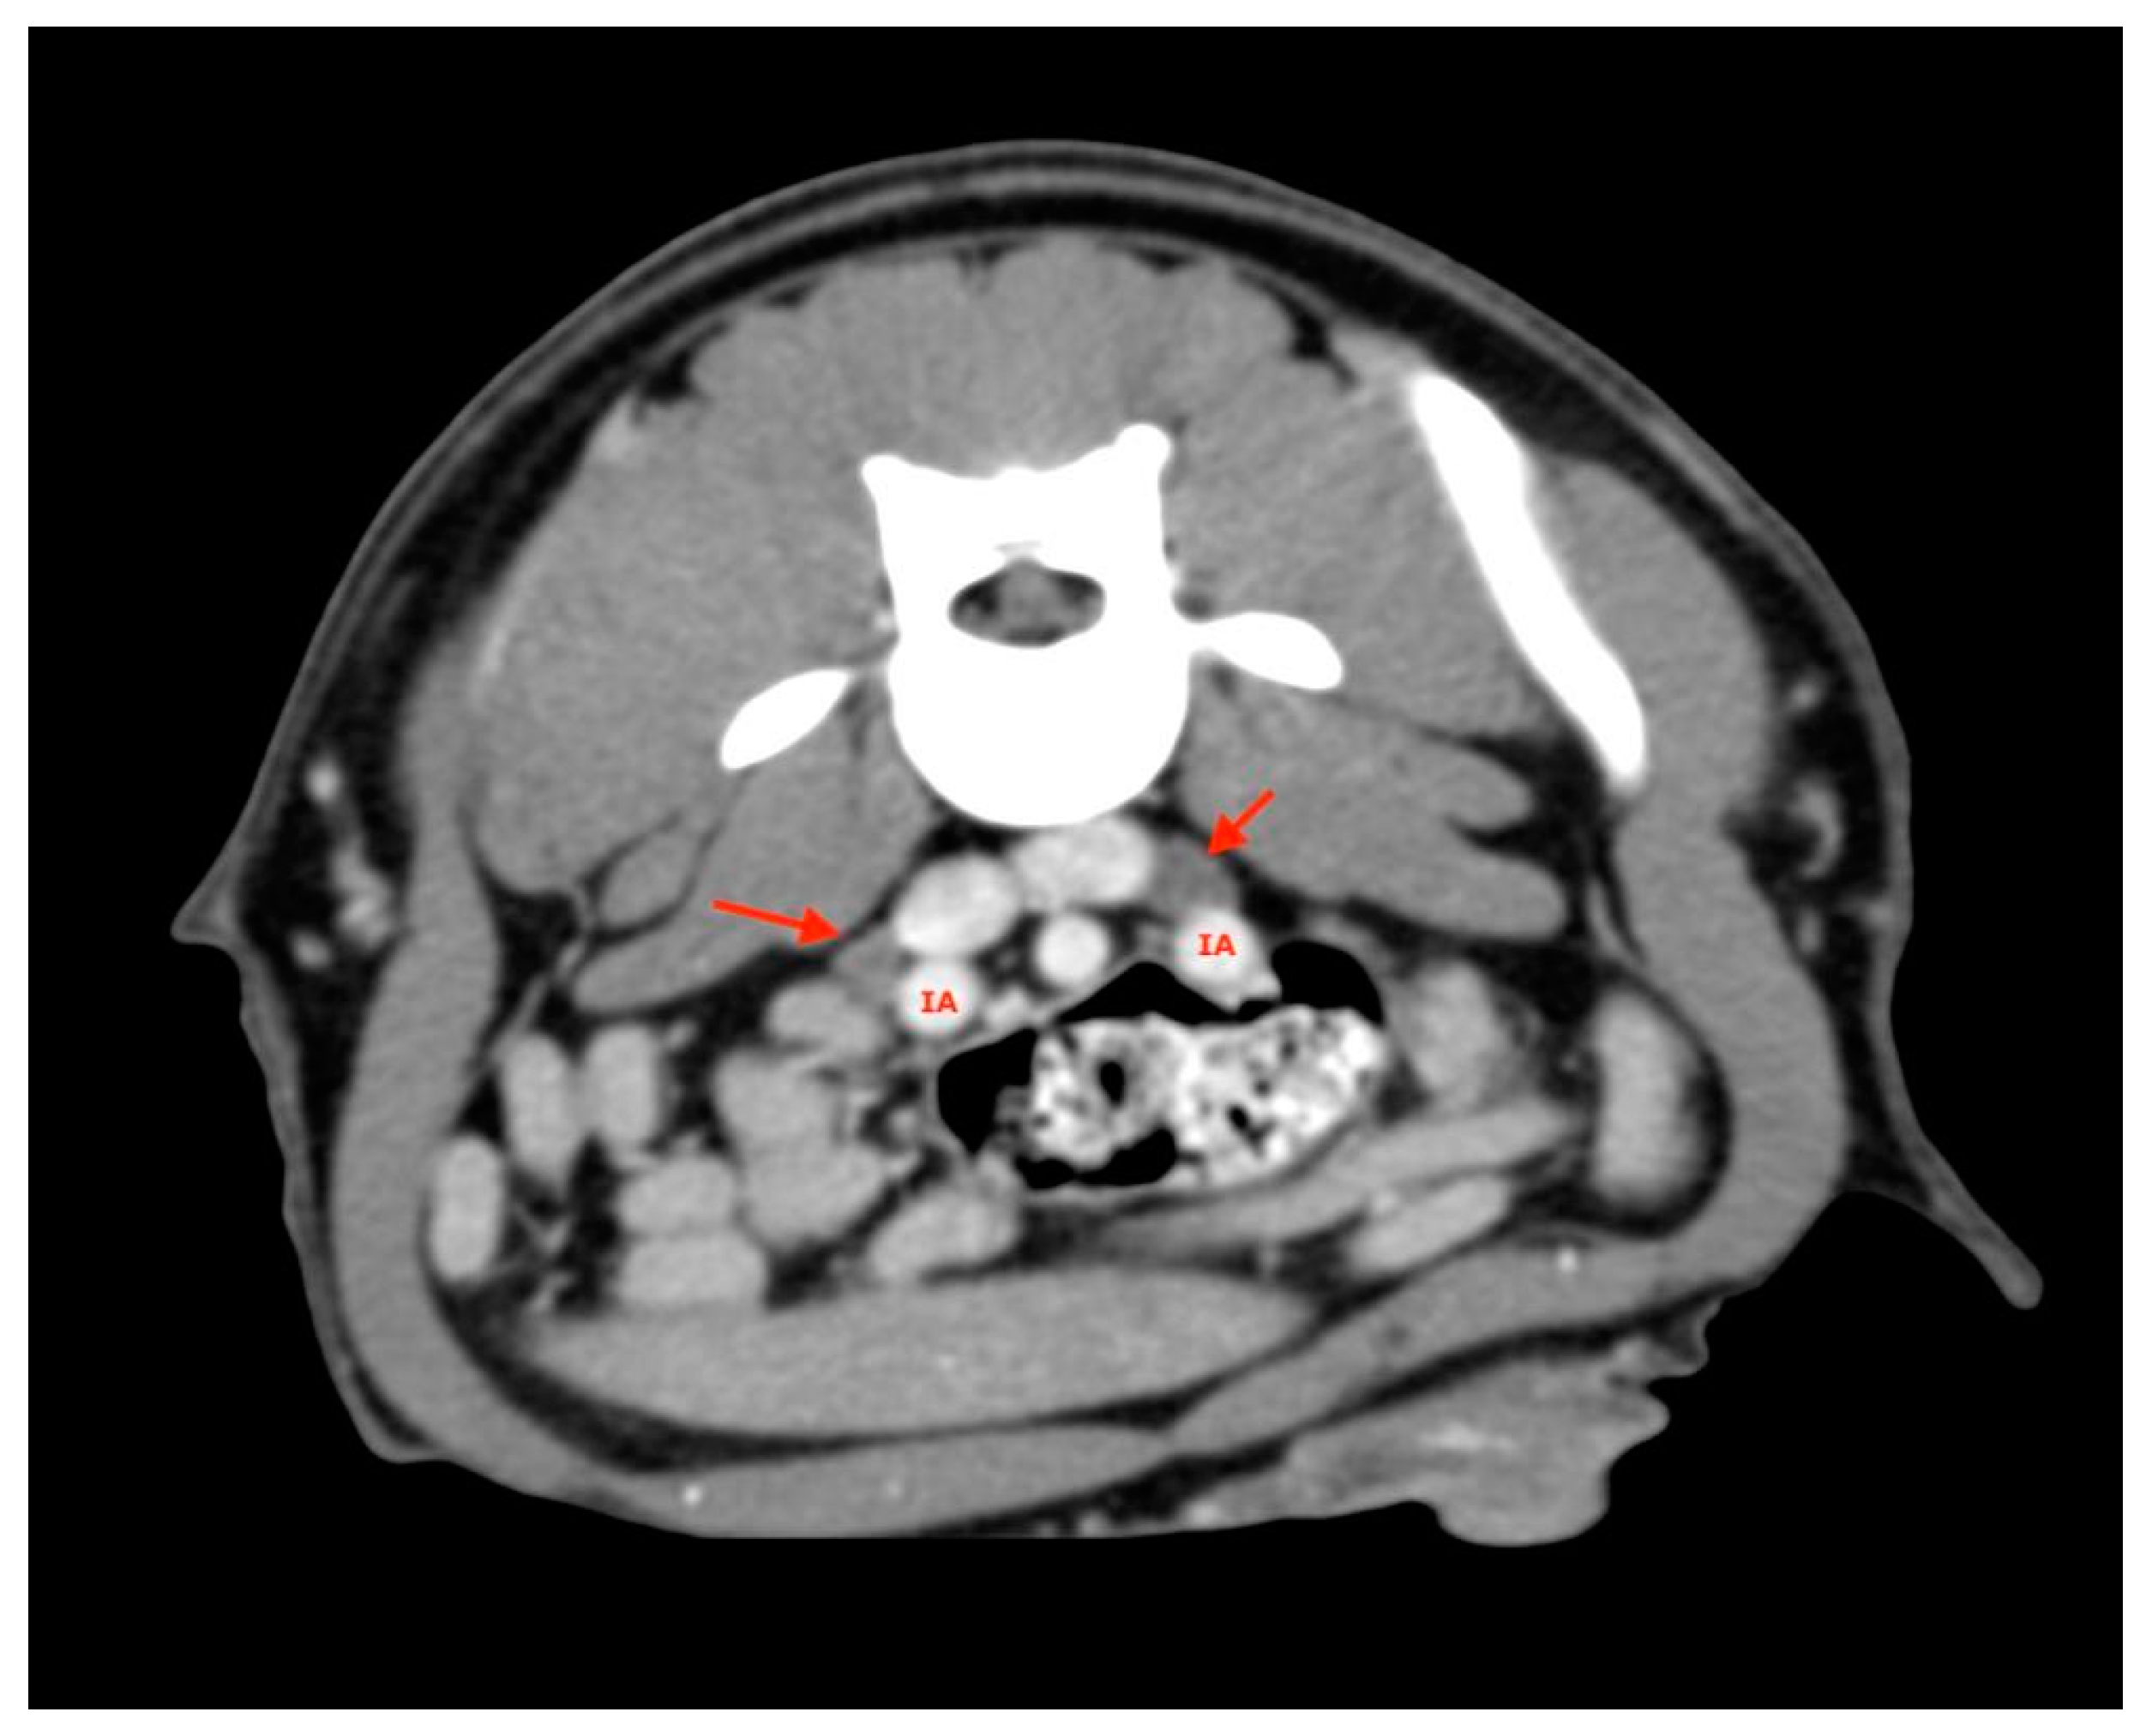

2.4. Procedures

2.5. Measurements